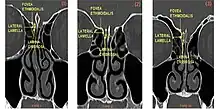

Keros classification

The Keros classification is a method of classifying the depth of the olfactory fossa.

The depth of the olfactory fossa is determined by the height of the lateral lamella of the cribriform plate. Keros in 1962, classified the depth into three categories.[3]

- type 1: has a depth of 1–3 mm (26.3% of population)

- type 2: has a depth of 4–7 mm (73.3% of population)

- type 3: has a depth of 8–16 mm (0.5% of population)

- type 4: has asymmetric depths (described by Stammberger)